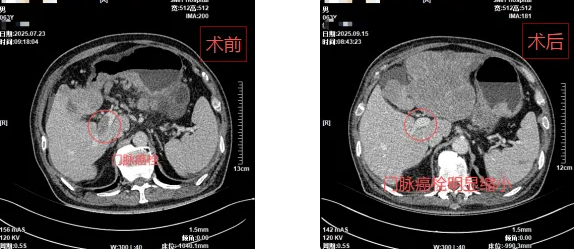

三个月后复查结果显示:患者肝胃病灶显著缩小,肿瘤标志物大幅降低,病情得到有效控制,疗效令人鼓舞。